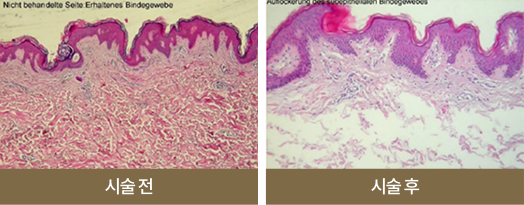

나이가 들수록 피부는 늘어지고,

근육은 약화됩니다.

또한, 얕게 혹은 깊게 분포되어 있는

지방이 중력 방향으로 이동하게 됩니다.

리프팅은 이동된 지방을 줄여주거나 원래의 위치 또는 필요한 방향으로 이동시킴과 동시에

약해지고 늘어진 피부와 근육의 장력을 강화시키는 복합적이고 입체적인 시술입니다.